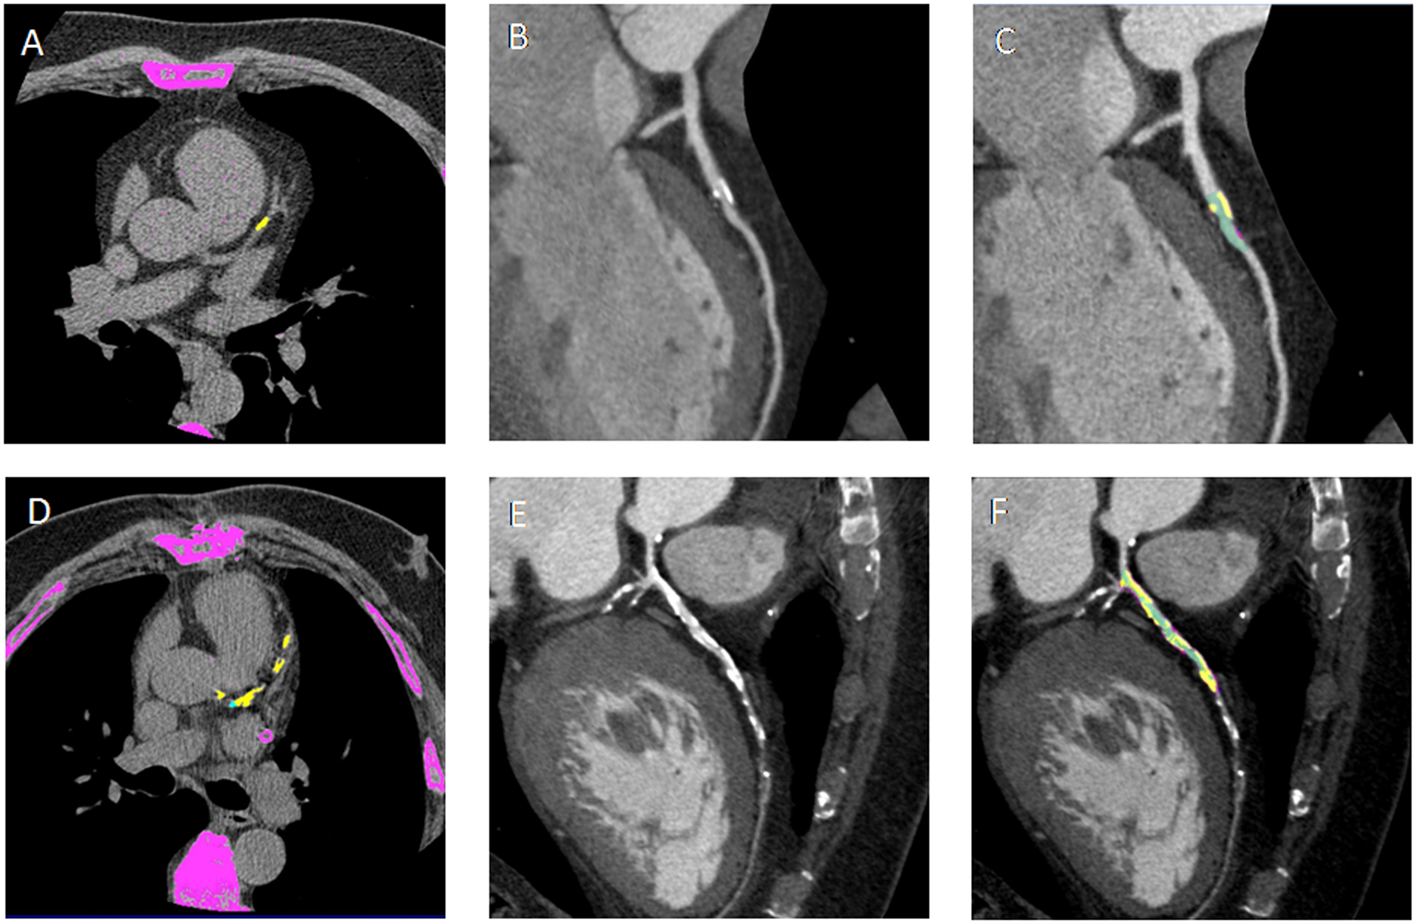

There was significant difference between DM−CAD+ and DM+CAD+ according to NCS and NSP (P = 0.026, P = 0.04, respectively). Cascore was significantly higher in DM+CAD+ compared to DM−CAD+ (Figures 1 and 2): 1,068.7 (517.2–2,086.85) vs 214.05 (72.98–970.15) P = 0.019. As regards plaque characterization, CPV was significantly higher in DM+CAD+ [105.85 (51.2–341.73) mm3] compared to DM−CAD+ [42 (7.2–105.9) mm3] P = 0.014, but there was no significant difference according to NCPV and TPV: 519.85 (411.93–1,064.85) mm3 for DM+CAD+ and 421.85 (240.10–689.58) mm3 for DM−CAD+ P = 0.37 and 688.95 (470.05–1,436) mm3 for DM+CAD+ vs 454.45 (257.78–820.83) mm3 for DM−CAD+ P = 0.16, respectively. RI was 1.40 ± 0.24 for DM+CAD+ and 1 ± 0.19 for DM−CAD+ P < 0.001, and plaque burden was 0.45 ± 0.14 for DM+CAD+ and 0.27 ± 0.15 for DM−CAD+ P < 0.001. Results are summarized in Table 2.

Figure 1. (A,D) Non-contrast enhanced images showing calcium deposits (yellow) on the left descending coronary artery (LAD) in a non-diabetic CAD patient (DM−CAD+) and in a diabetic CAD patient (DM+CAD+), respectively. (B,E) cMPR of LAD is provided for DM−CAD+ and DM+CAD+. (C,F) Plaque characterization: the calcific (yellow) and non-calcific (pink) components of the plaque are highlighted; the vessel lumen is represented in green. DM+CAD+ displayed significantly higher coronary calcium values compared to DM−CAD+.

Calcium score, CPV, plaque burden, and RI were significantly higher in DM+CAD+ compared to DM−CAD+. Previous studied have examined CAD and plaque features in diabetic patients by CTCA. Diabetics showed extensive coronary artery calcium deposits and, therefore, a larger atherosclerotic plaque burden with a consequent higher risk for all-cause mortality than in non-diabetic patients (5, 47–54). Gao et al. (47) found that diabetics compared to non-diabetics have higher total coronary artery calcium, a higher proportion of coronary segments with plaque and multivessel obstructive disease. In a study by Van Werkhoven et al., obstructive CAD and the number of diseased segments, with obstructive and non-obstructive plaques, were higher in diabetics than non-diabetics. Total Agatston score was higher in diabetic patients (440 ± 786 vs 195 ± 404, P < 0.001) (5). Khazai et al. found that segment involvement score, segment stenosis score, and total plaque score were higher in diabetics but there was no significant difference in the number of non-calcified plaque between the two groups (50). In one study by Pundziute et al., diabetics showed more diseased segments and more segments with non-obstructive CAD, but Agatston score was similar between the two groups (54). Furthermore, Chu et al. detected more calcified plaques than mixed or non-calcified plaques in diabetics. Among the different degrees of stenosis, mild narrowing was most common, and no significant difference between non-obstructive stenosis and obstructive stenosis was observed (48). In agreement with the aforementioned works, in our study, DM+CAD+ presented more diseased coronaries in terms of coronary calcium, significant stenoses, atherosclerotic burden, and extent of disease. Furthermore, we have quantified RI in diabetic patients by CTCA providing an additional prognostic value comparable only to invasive procedures such as intravascular ultrasound (55, 56). A recent study analyzed CAD features comparing hypertensive, dyslipidemic, and diabetic patients by CTCA reporting the prevalence of positive remodeling as a qualitative parameter (57).